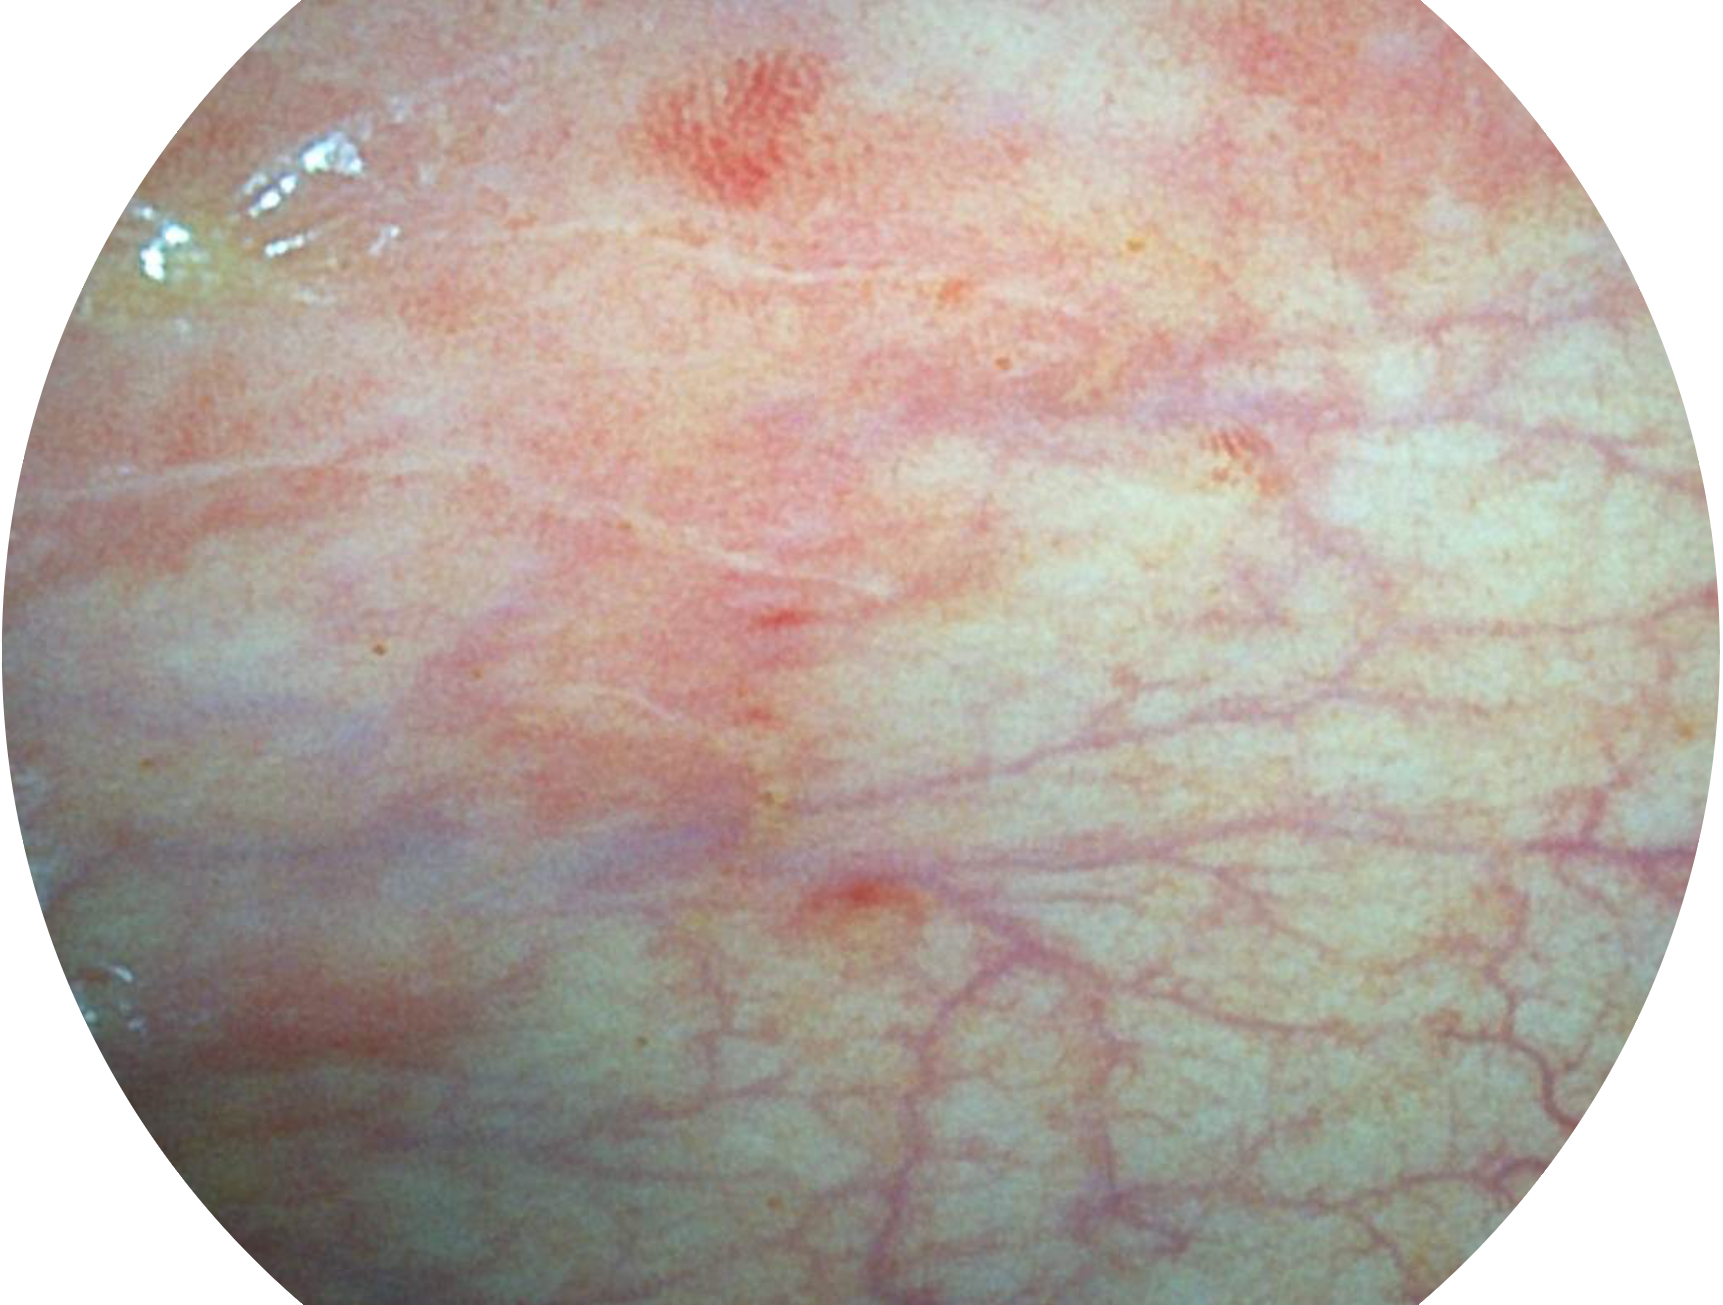

百老汇电子游戏官网新开发的内镜染色技术,主要是基于多波长LED 光源的开发,VLS-55Q 四波长LED 光源是由四个不同颜色的LED光按照相应照明模式所规定的特定发光比例进行合束后形成,合束后形成的照明光的光谱由红光、绿光、蓝光及蓝紫光这四个不同的波段范围构成。具有更高光谱自由度,通过光谱比例的控制,实现了聚谱成像技术,英文全称为“Spectral Focused Imaging, SFI”,缩写为“SFI”和光电复合染色成像技术,英文全称为“Versatile Intelligent Staining Technology, VIST”,缩写为“VIST”。